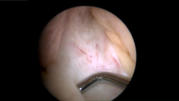

Arthroskopie =

Gelenkspiegelung

Arthroskopie = Gelenkspiegelung